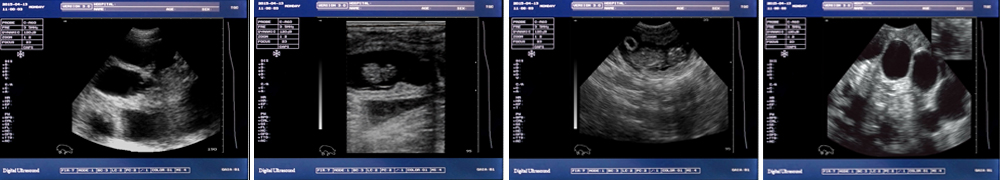

一流的數字成像技術,圖像更清晰